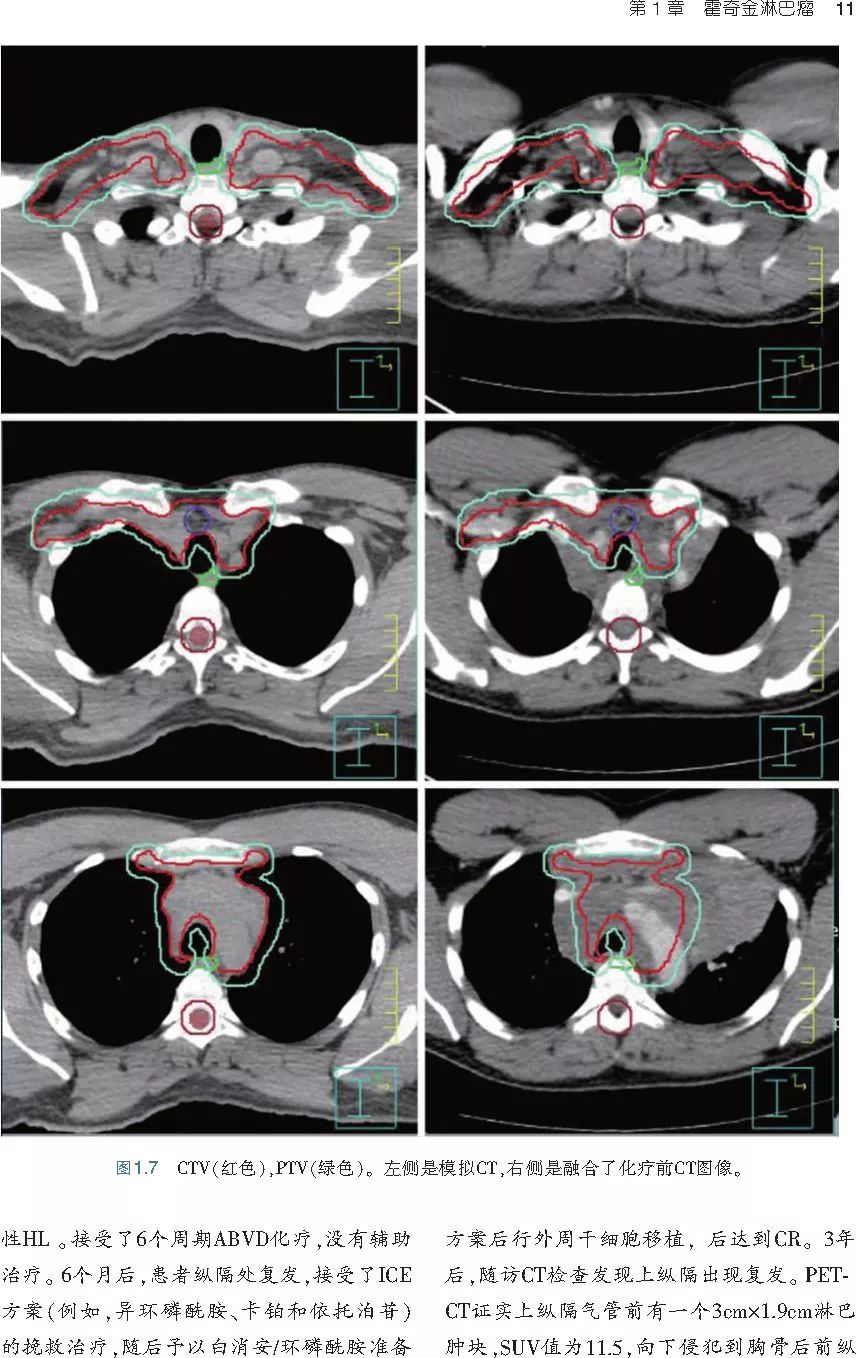

本书旨在帮助临床医生对常见血液系统恶性肿瘤疑难病例进行管理,包括霍奇金淋巴瘤、非霍奇金淋巴瘤和白血病患者,并通过多个病例进行阐述。案例讨论遵循标准格式,包括临床描述,其次是与诊断相关的病理描述和分期,然后详细讨论治疗选择。最后,确定治疗方案,并提供所使用的规划放疗技术/方式的图像。对放射肿瘤医生进行临床决策非常有帮助,对于血液病临床医生也有很好的指导作用。

近年来,放射治疗技术得到了迅速发展,调强放疗、图像引导放疗及其他新技术方法等,对恶性肿瘤治疗产生了巨大影响。现代放疗技术使精确定位、靶区勾画及给量成为可能,实现了肿瘤局控率和生活质量的双赢,对血液系统恶性肿瘤的临床治疗也产生了一定的影响。此书内容上不仅反映了血液系统恶性肿瘤综合治疗的进步,更是对其中放射治疗的新变化进行了系统、详细的阐述,这对当前血液系统恶性肿瘤放射治疗临床实践具有非常好的指导作用和参考价值。